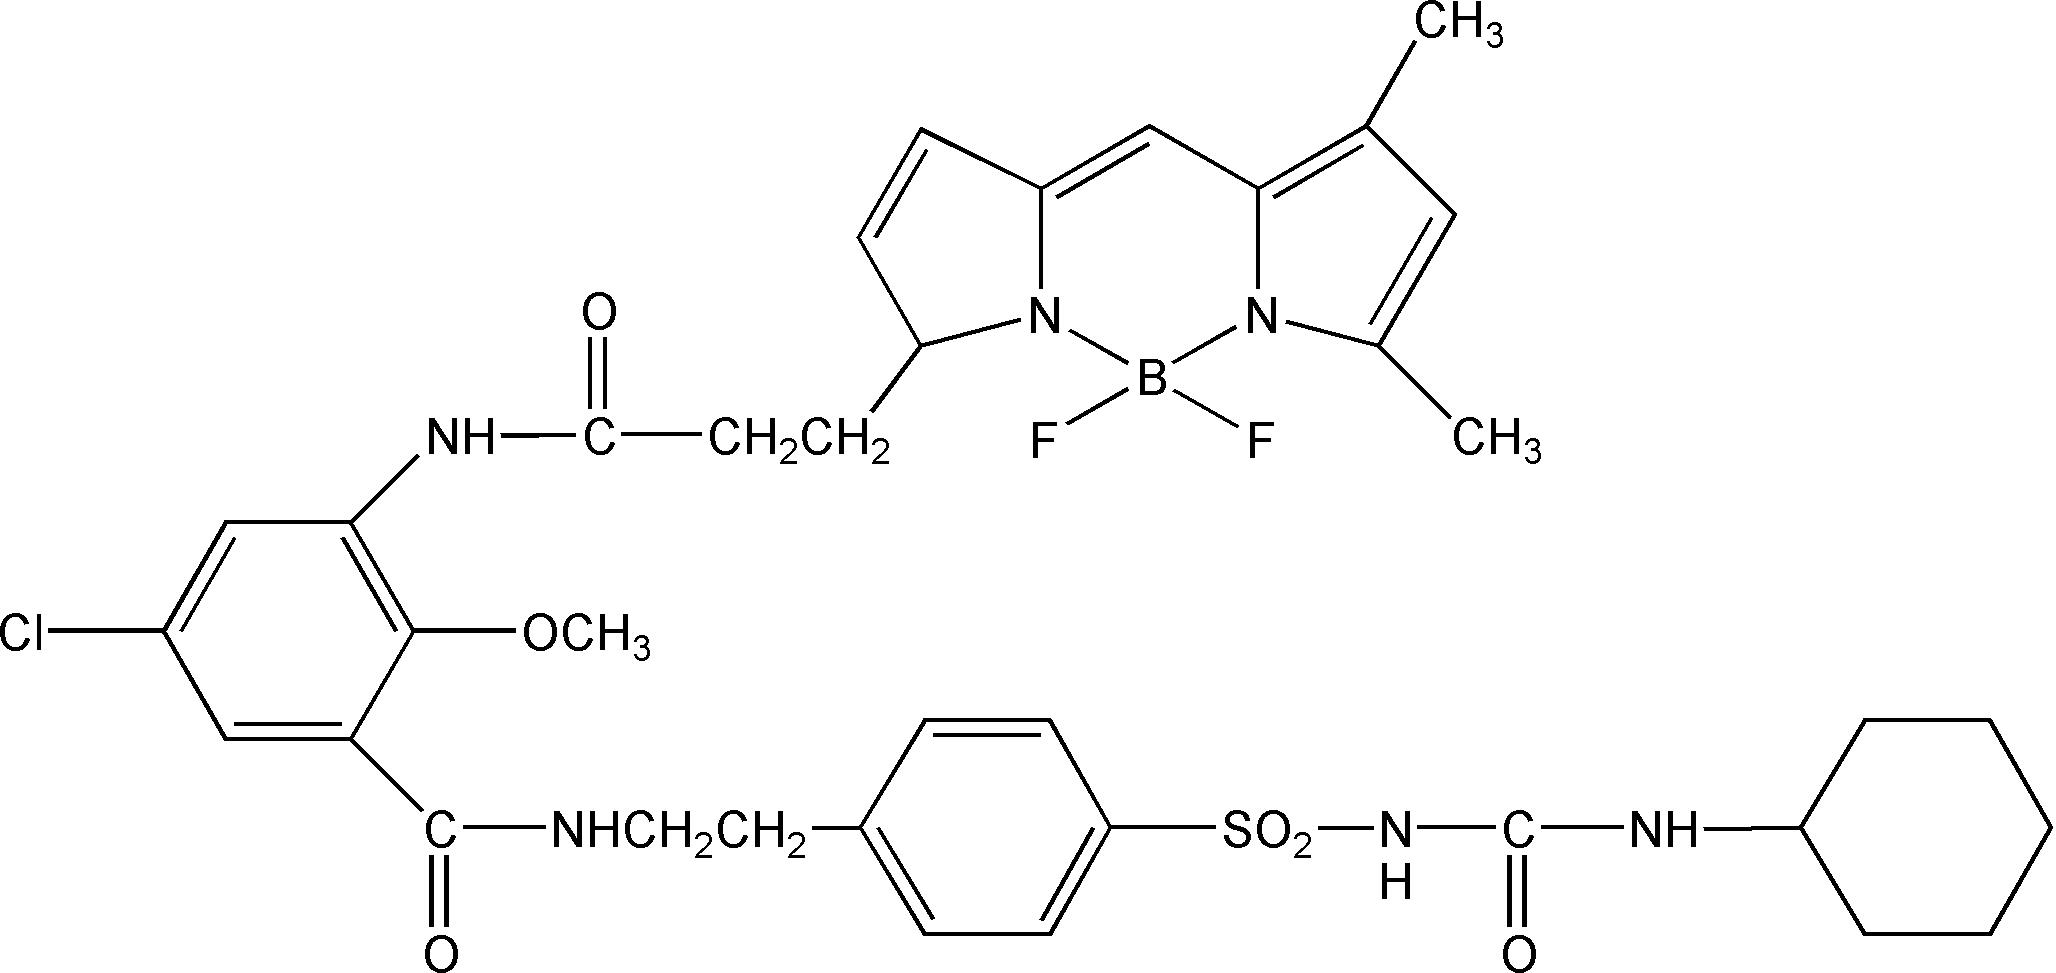

MDL Number: - MF(分子式): C37H42BClF2N6O6S MW(分子量): 783.0952

| 分子式 Formula | C37H42BClF2N6O6S |

| 分子量 Molecular Weight | 783.0952 |

| 分子式 | C26H21F5N4O4S | C37H42BClF2N6O6S | C44H42BClF2N6O7S2 |

| 產品說明 | ER-Tracker Green(BODIPY FL 格列本脲)探針是一種具有細胞通透性的活細胞染色劑,對內質網 (ER) 具有高度選擇性染料,不像傳統的DiOC6(3),該染色劑由發綠色熒光的 BODIPY? FL 染料和格列本脲組成。 |